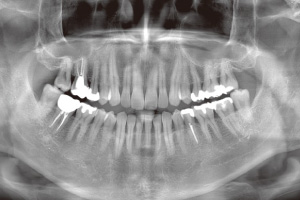

レントゲンで確認

歯の根の中に薬を入れた後、薬が根の先までしっかり入っているかレントゲンで確認します。薬剤がぴったりとすきまなく入っていないと、痛みや再感染の原因となってしまうため再度入れ直すこともあります。

レントゲン撮影をし、薬が歯の根の中に完全に入っていることを確認できたら、土台となるコアを入れ、被せ物(クラウン)を装着し、治療終了です。